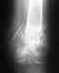

За неимением в настоящее время хирургов (перид отпусков в г.Мурманске)необходима консультация специалиста.После последнего операционного вмешательства 21,06,2112 (восстановление двигательной функции кисти и пальцев левой руки после гидравлического сжатия левого предплечья) не проходящий отёк кисти с ограничуной подвижностью постоянная боль большой,указательный,средний палец.